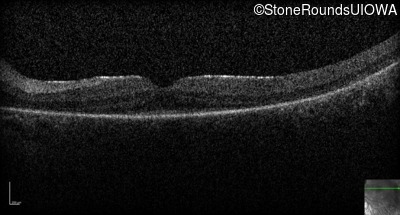

Optical Coherence Tomography - Left -

No Light Perception

Exemplar

Expanded OCT Stack

×